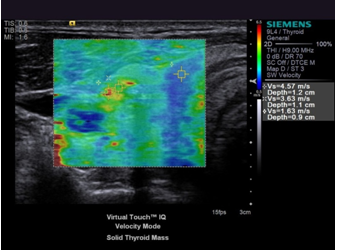

В основу волновой эластографии заложена возможность исследования эластичности мягких тканей. В отличие от доброкачественных опухолей, злокачественные — плотные, не эластичные и с трудом поддаются компрессии. На мониторе аппарата УЗИ более плотные ткани окрашены в голубой и синий цвета, жировая ткань приобретает желто-красный оттенок, а соединительная ткань — зеленый. Высокая специфичность метода позволяет избежать необоснованных биопсий. После прохождения УЗИ с эластографией пациент получает на руки развернутое заключение, в котором врач описывает: размер и положение исследуемого органа, наличие, размер и плотность новообразований, наличие и стадию фиброзных изменений, рекомендации по дальнейшему наблюдению у нужного специалиста.